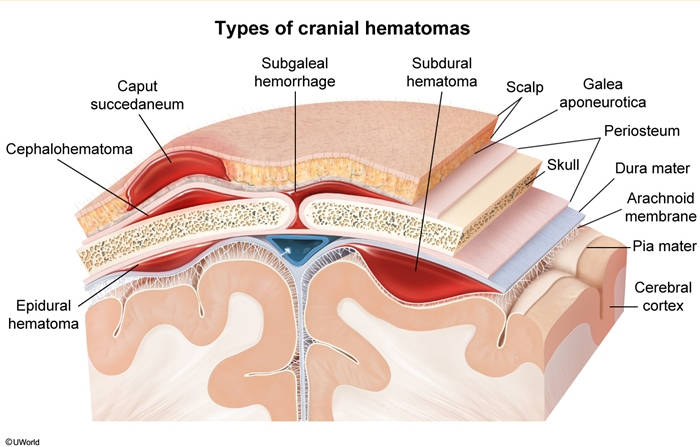

cephalohematoma is ____ bleeding

subperiosteal, does not cross suture lines - firm, nonfluctuant

subgaleal vein shearing is ___ (peds)

hemorrhage involving the dural sinuses & scalp, leading to massive blood accumulation between the periosteum and galea aponeurotica

diffuse, fluctuant scalp swelling that extends beyond suture lines and potentially to the neck; expands over 2-3 days, can lead to hypovolemic shock, DIC, and death → supportive care required